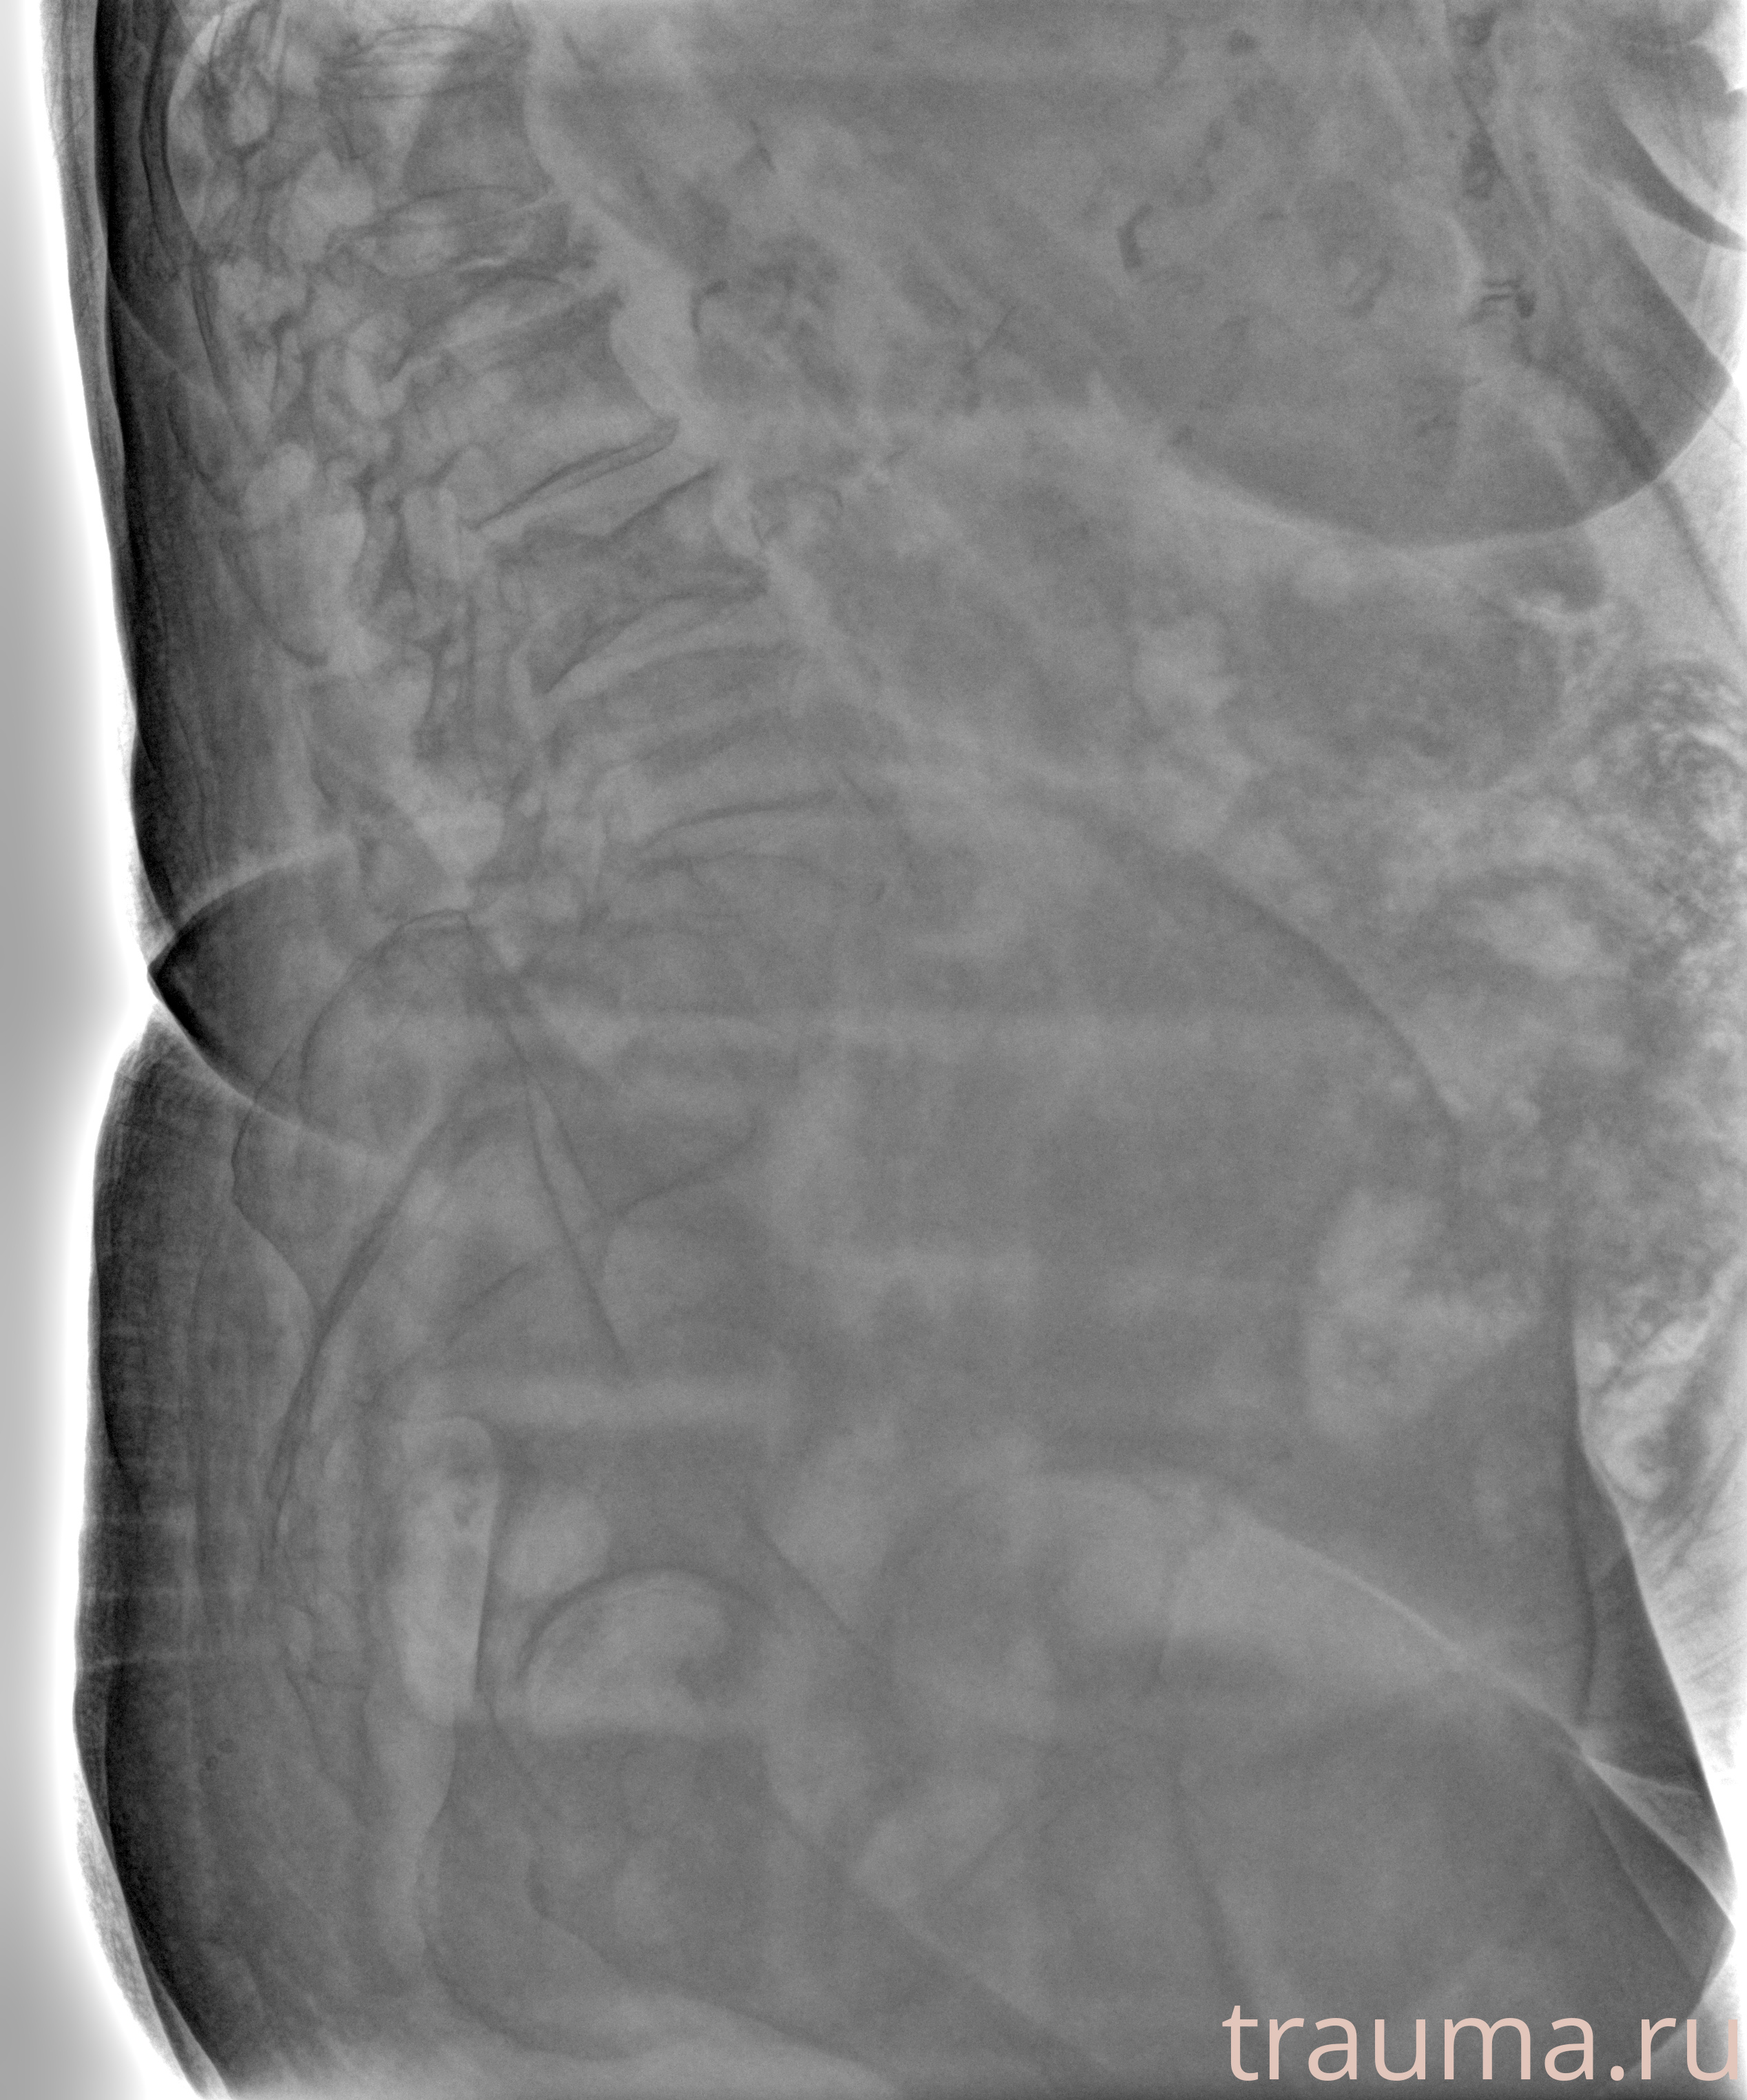

Рентгенограммы

Рентген на дому: по вашему адресу приезжает врач-рентгенолог, травматолог-ортопед с мобильным рентгеновским аппаратом, проводит диагностику травмы или заболевания, делает необходимые рентгенограммы, дает рекомендации по дальнейшему лечению. Получить качественные снимки в домашних условиях возможно благодаря уникальной методике, разработанной МосРентген Центром для института  Склифосовского

Яркость: 1   Контраст: 1   Инвертировать: 0 Увеличение: 1

Перетаскивайте мышь вверх/вниз для контраста, влево/право для яркости. Прокрутка колесом изменяет масштаб. Нажмите Сбросить для возврата к исходному изображению. При увеличении держите мышь в той области, которую хотите рассмотреть.